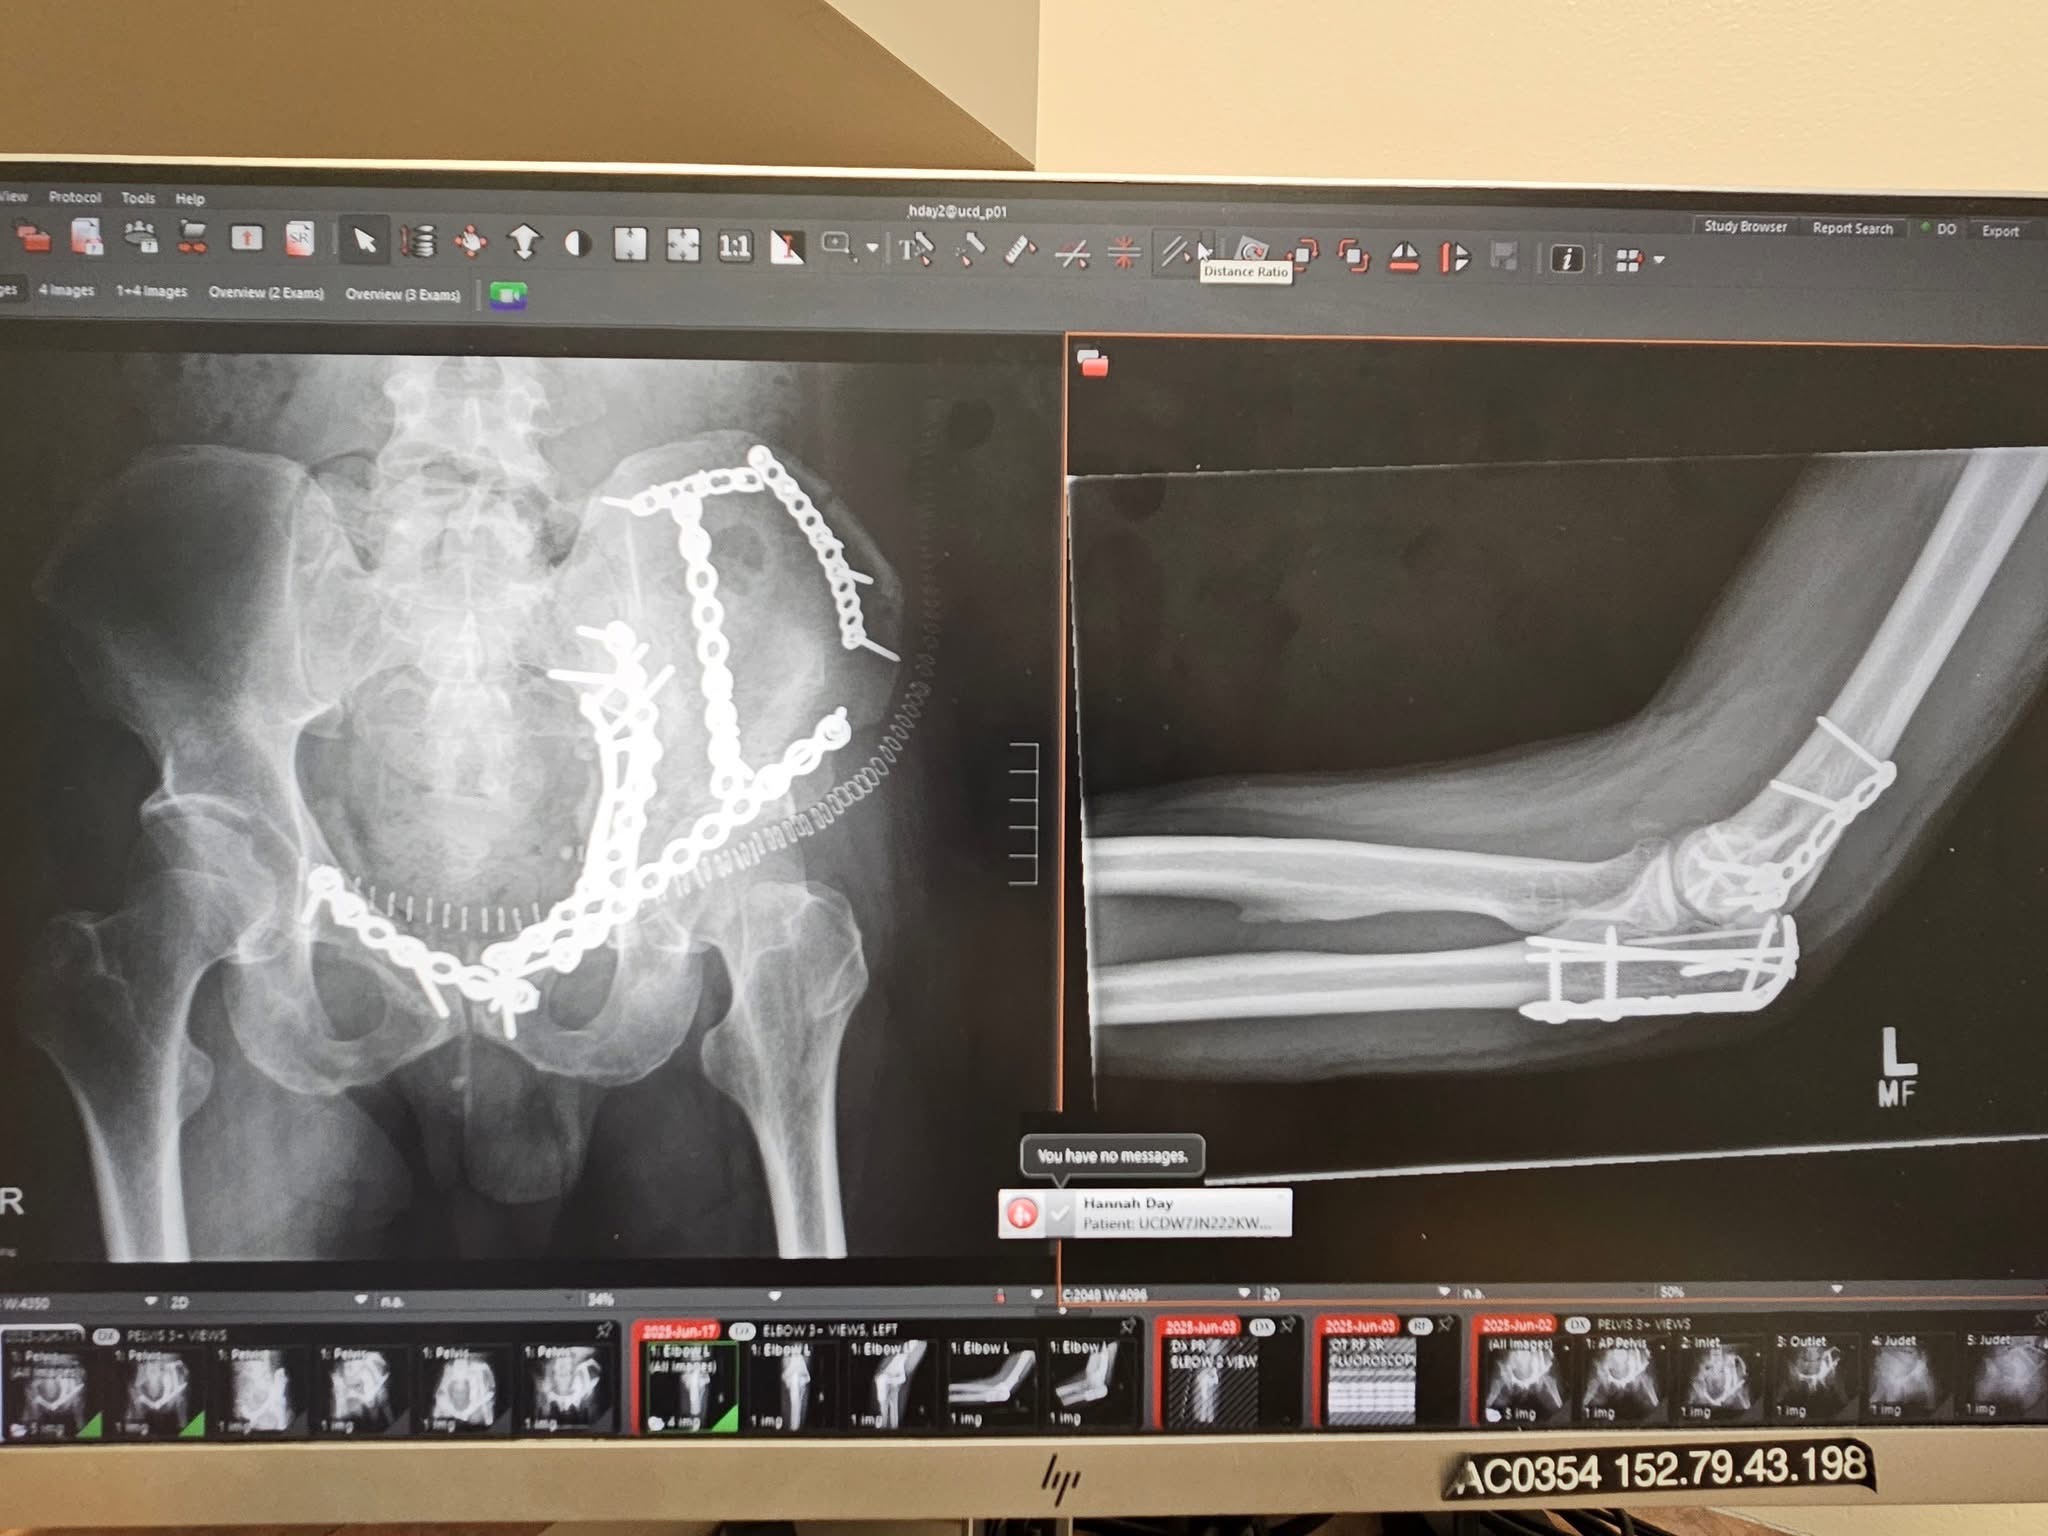

On May 24, 2025, while bravely attempting to repair the restaurant’s air conditioner, Robert suffered a tragic 30-foot fall from the roof. He is now fighting through severe injuries, including a shattered pelvis, broken arm, and fractured knee. As a single father of four, Robert’s world revolves around his children and his passion for serving our community through his vibrant restaurant.